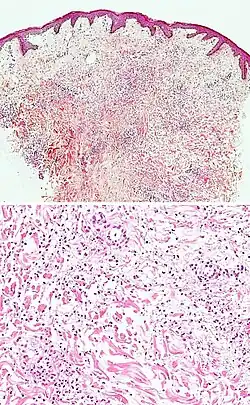

| Pigmented purpuric dermatosis |

|

| Secondary syphilis | Various, but often one or a combination of:[21]